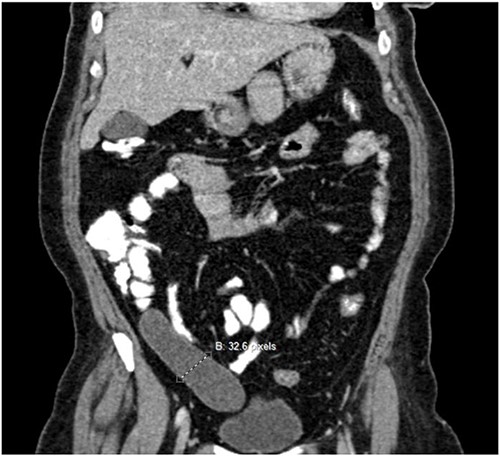

Abdominal ultrasound and computerized tomography (CT) scan demonstrated a cystic tumor, 13 × 3 cm, in the right abdomen dorsal to the cecum and the ascending colon. No lymph node swelling or fluid collection was illustrated in Fig. 1.

Pre-operative Computed tomography scan showing appendix mucocele.